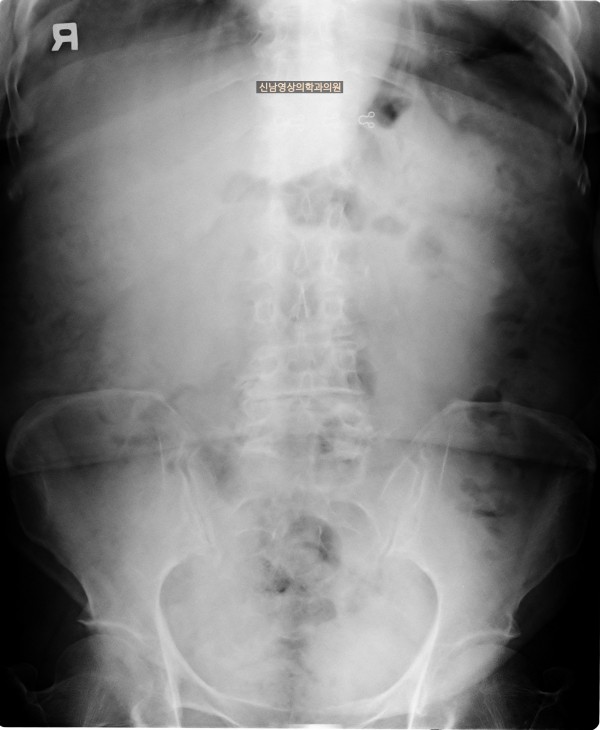

본 환자분은 변비가 지속되면서 좌하복부 통증이 있으셨던 분으로 본원에서 복부 초음파 검사를 진행하였습니다.

하행 결장 부위에서 장이 두꺼워진 소견이 보여 진행된 대장암의 가능성이 농후해보여 대학병원으로 전원해 대장내시경을 받고, 수술로 2기암으로 진단되신 케이스입니다.